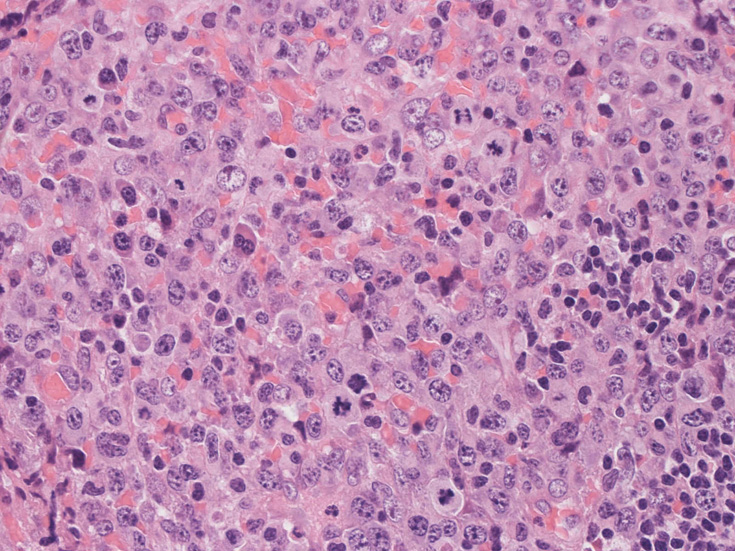

腹膜脂肪組織内から生検されたリンパ節は基本構造を失っている。低倍率のHE所見では異型細胞が不鮮明な結節構造を形成して増殖している。一次リンパ濾胞を腫瘍細胞が置換しているように見える所見がある。

高倍率x400では, 増殖細胞はcentroblastに似て複数の明瞭な核小体をもった淡明な大型類円ないし卵円形核を持っている。核分裂像が多い。この症例では多型はめだたない。典型的な腎臓型のくびれた核を持つ細胞などはない。ALKの形態的variant症例と考えられるが, 化学療法後の再発による影響も否定できない。